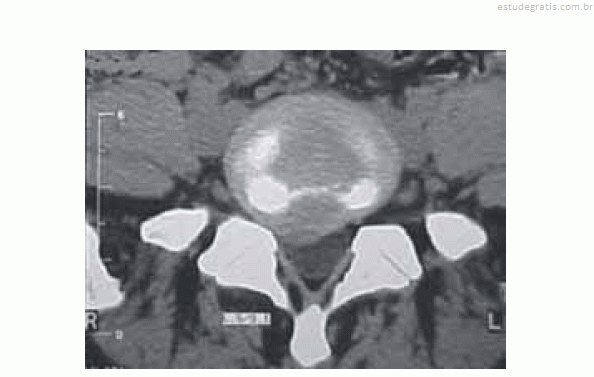

Um empregado de uma fábrica de móveis com 47 anos de idade queixa-se, há algum tempo, de lombalgia, mas continua trabalhando normalmente. Certo dia, teve queda de cima de um caminhão e não conseguiu mais andar devido à dor na região lombar e no membro inferior à direita; ficou em repouso por uma semana, mas continuou com os sintomas álgicos. Voltou ao serviço médico quando realizou novo exame físico, sendo constatadas algumas alterações. O médico solicitou uma tomografia computadorizada (TC) da coluna lombar, cuja imagem é reproduzida abaixo, e o encaminhou ao neurologista.